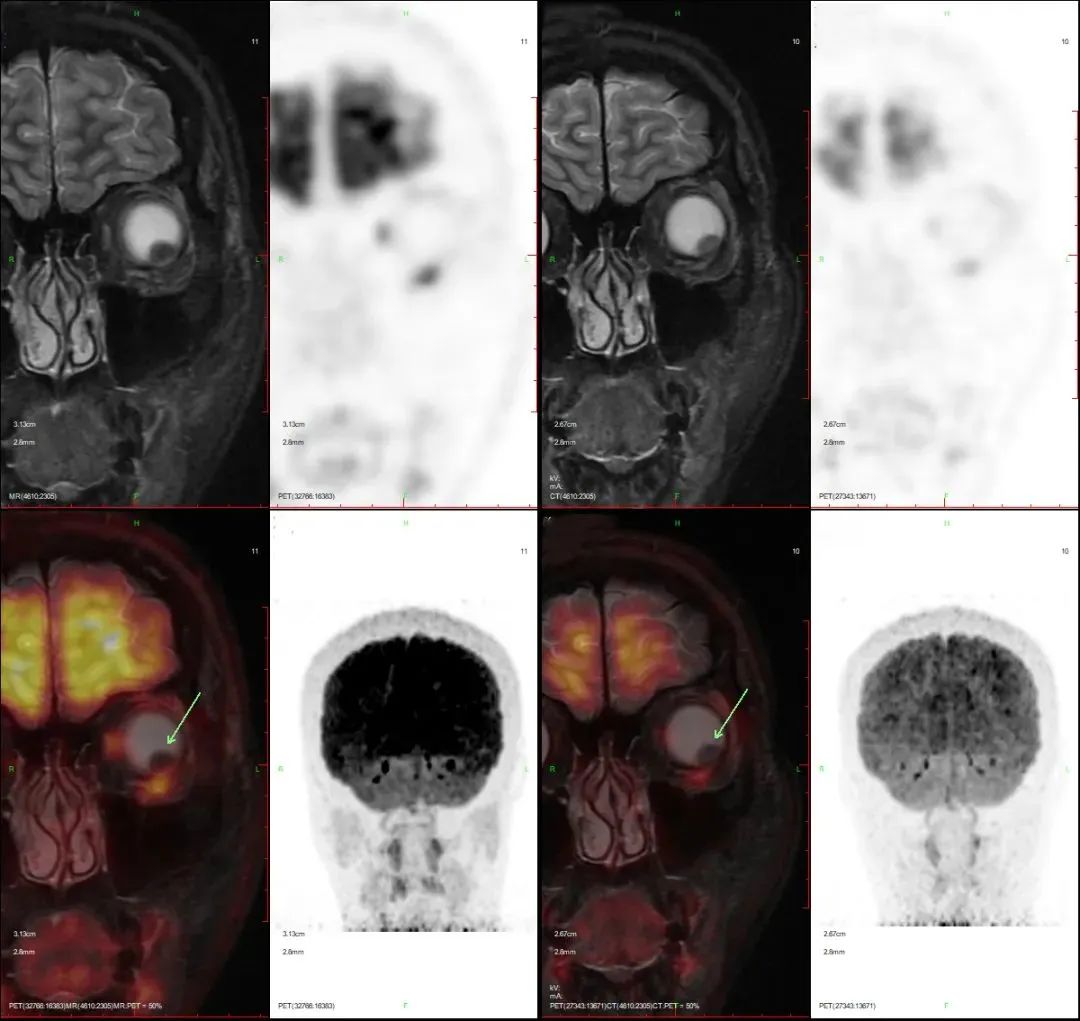

不久前,筱洁(化名)来到中心进行PET/CT 全身及PET/MR局部扫描复查,检查影像资料及诊断结果如下:

检查所见:

头颈部:左眼黑色素瘤粒子重离子放疗后:左眼球轮廓清晰,左眼环后外侧壁结节状增厚,大小约8 ×5mm(原大小约9mm×6mm),FDG轻微代谢增高,SUVmax 1.7(原SUVmax 2.4),延迟局部PET/MRI 示病灶呈结节状T2WI等低信号,T1WI高信号,STIR呈低信号,边缘光整,FDG代谢升高,SUVmax 5.9 (原SUVmax 5.7),眼环外间隙较清。

检查结论:

a.左眼黑色素瘤粒子重离子放疗后,对比2022.1.10核医学检查:左眼环后外侧壁结 节状增厚,大小较前略缩小、FDG代谢较前大致相仿,考虑病变稍有退缩、肿瘤活性仍存,请结合临床;

b.余全身PET/CT扫描(包括脑)未见FDG高代谢肿瘤累及(或转移)病灶。

自确诊后,筱洁(化名)就开始行粒子重离子放疗, 通过坚持不懈地与病魔奋斗,这次扫描临床诊断结果显示目前状态良好:原病灶较前略有退缩,且全身其他部位没有看到肿瘤累及或转移灶。